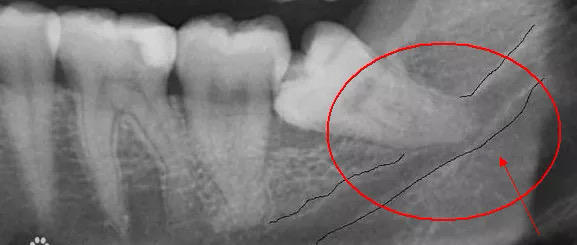

第三,智齿对邻牙造成严重影响。当智齿生长空间严重不足,更坏的可能是出现阻生智齿,即没有按正常垂直方向生长的智齿。阻生智齿不仅会引发自己 周边牙龈炎症,更有可能对邻牙施力,导致原本整齐的牙齿移位,甚至导致邻牙的龋坏,这就是医生常说的"好牙都被顶坏了",这种情况下当然要趁早就医,及时拔出,保住好牙。